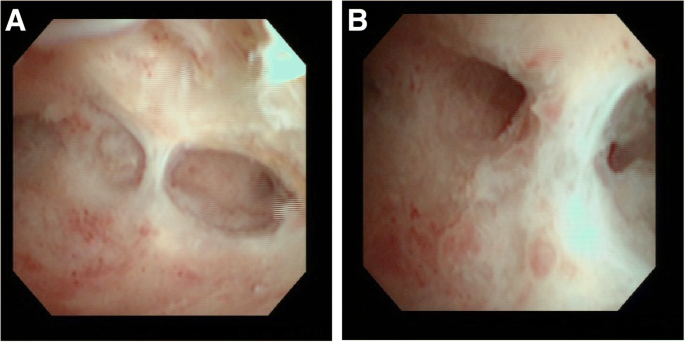

Adezyonların kanıtı ve uterus mukozasının değerlendirilmesi histeroskopik olarak gerçekleştirilir.